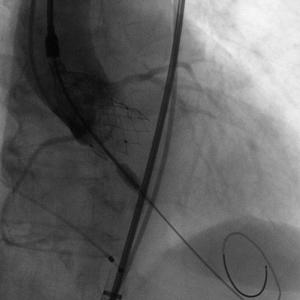

Numed18球囊扩张

瓣膜释放01

瓣膜释放02

释放后造影